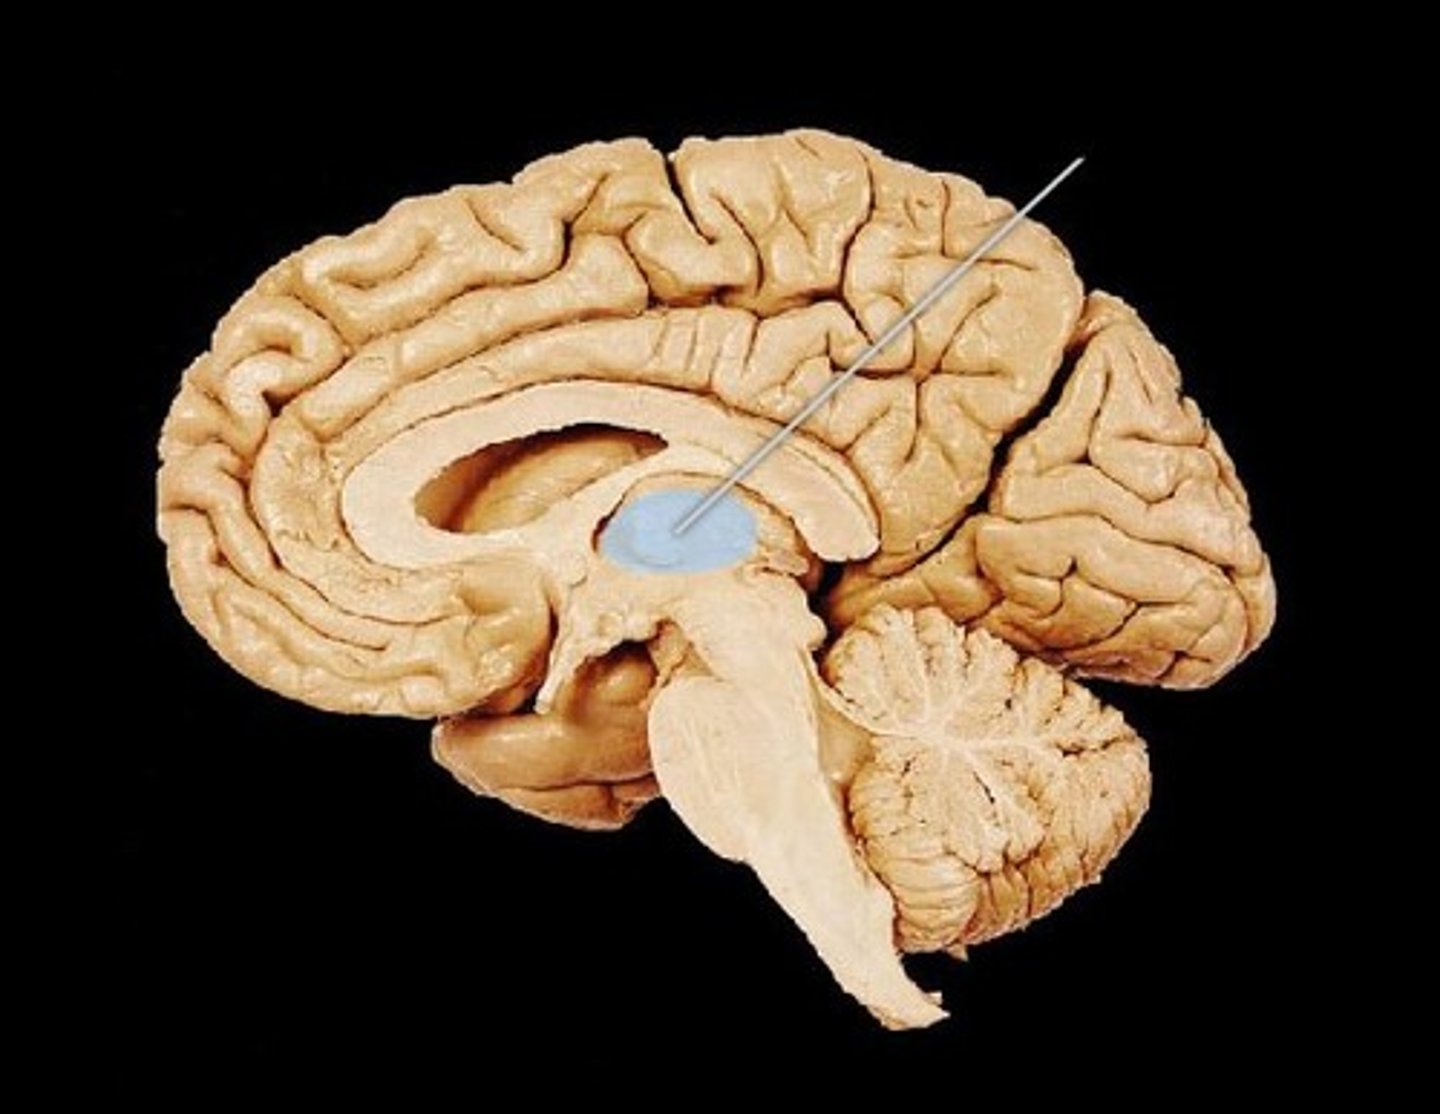

Corpus callosum

Fornix

Septum pellucidum

Pineal Gland

Arbor Vitae

Cerebellum

pons

Pituitary Gland

Thalamus

Hypothalamus

Cerebral Aqueduct

Medulla Oblongata